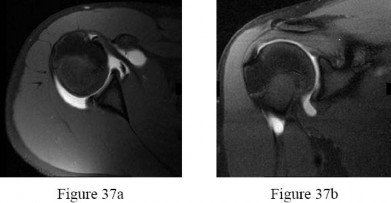

Dr. Mohammed Hutaif

Medically Verified Content by

Prof. Dr. Mohammed Hutaif

Consultant Orthopedic & Spine Surgeon